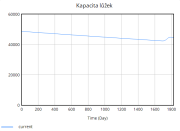

| 22:34, 15 June 2025 | 1 KapacitaLůžek.png (file) |  |

7 KB | Kozo01 | 1 | |